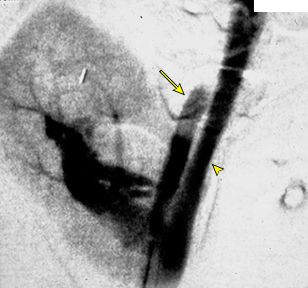

7/ Pain lasting more than 12 hours - 4 %;

due to ureteral obstruction from a blood clot or

stretching of the renal capsule by a subcapsular hematoma

Image: Ureteric obstruction due to blood clot

link.springer.com/article/10.100…